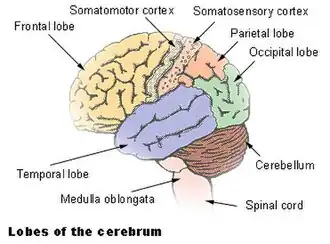

O córtex motor primário (área 4 de Brodmann) é uma região cerebral que, nos seres humanos, está localizada na porção dorsal do lobo frontal. É a região primária do sistema motor e trabalha em associação com outras áreas motoras, incluindo o córtex pré-motor, a área motora suplementar, o córtex parietal posterior e várias regiões do cérebro subcortical, para planejar e executar movimentos. [1] O córtex motor primário é definido anatomicamente como a região do córtex que contém grandes neurônios conhecidos como células Betz. As células de Betz, juntamente com outros neurônios corticais, enviam axônios longos pela medula espinhal para sinapse nos circuitos interneurônios da medula espinhal e também diretamente nos neurônios motores alfa na medula espinhal que se conectam aos músculos.[2]

Estrutura

O córtex motor primário humano está localizado na parede anterior do sulco central. Ele também se prolonga para fora do sulco parcialmente para o giro pré-centrado. Anteriormente, o córtex motor primário é limitado por um conjunto de áreas que se encontram no giro pré-central e que geralmente são consideradas para compor o córtex pré-motor lateral. Posteriormente, o córtex motor primário é delimitado pelo córtex somatossensorial primário, que fica na parede posterior do sulco central. Ventralmente, o córtex motor primário é limitado pelo córtex insular no sulco lateral. O córtex motor primário se estende dorsalmente até o topo do hemisfério e depois continua na parede medial do hemisfério.

Função

Existe uma representação amplamente somatotópica das diferentes partes do corpo no córtex motor primário em um arranjo chamado homúnculo motor (latim: pessoa pequena).[5] A área da perna está localizada perto da linha média, nas seções interiores da área do motor dobrando a fissura longitudinal medial. O lado lateral e convexo do córtex do motor primário é organizado de cima para baixo em áreas que correspondem às nádegas, torso, ombro, cotovelo, pulso, dedos, polegar, pálpebras, lábios e mandíbula. A área do braço e do motor de mão é a maior, e ocupa a parte do giro pré-central entre a área da perna e do rosto.